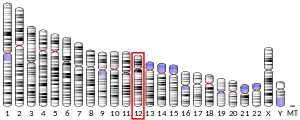

Aldehyde dehydrogenase, mitochondrial is an enzyme that in humans is encoded by the ALDH2 gene located on chromosome 12.[5][6] ALDH2 belongs to the aldehyde dehydrogenase family of enzymes. Aldehyde dehydrogenase is the second enzyme of the major oxidative pathway of alcohol metabolism. ALDH2 has a low Km for acetaldehyde, and is localized in mitochondrial matrix. The other liver isozyme, ALDH1, localizes to the cytosol.[7]

The ALDH2 gene is about 44 kbp in length and contains at least 13 exons which encode 517 amino acid residues. Except for the signal NH2-terminal peptide, which is absent in the mature enzyme, the amino acid sequence deduced from the exons coincided with the reported primary structure of human liver ALDH2. Several introns contain Alu repetitive sequences. A TATA-like sequence (TTATAAAA) and a CAAT-like sequence (GTCATCAT) are located 473 and 515 bp, respectively, upstream from the translation initiation codon.[9] In mice the official full name of the gene is aldehyde dehydrogenase 2, mitochondrial, and it is positioned on chromosome 5. It has 12 exons and the coding sequence is 1,560 base pairs.[10]